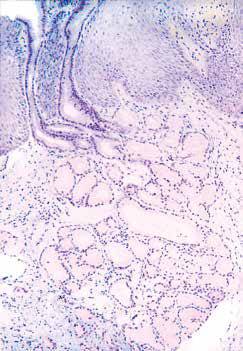

食管中段。食管上皮基底层细胞缺乏糖原,与其上层覆盖的糖原丰富细胞易于鉴别(PAS染色)。

食管贲门型腺体位于固有层内。导管内衬胃小凹样上皮细胞。

导管内衬细胞可能经过不同的距离延伸至复层鳞状黏膜上方(PAS-D)。

这些腺体呈PASD 染色阳性,pH 值2.5 的阿辛蓝染色阴性,表明具有中性黏液的特征。

黏膜下腺PAS-D 及pH值2.5 的阿辛蓝染色均呈阳性,具有酸性黏液的特征。